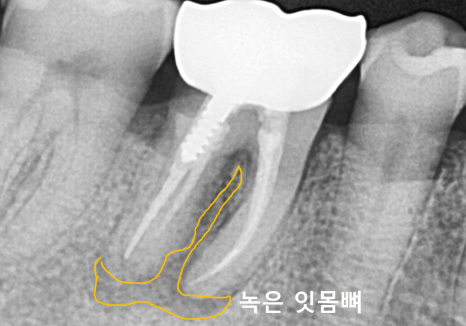

정확한 상태를 확인하기 위해

방사선 사진과 CT를 확인해 보았습니다.

역시나 뿌리 끝에 염증이 광범위하게 퍼져

까맣게 뼈가 녹아있는 모습을 볼 수 있었는데요...

안타깝지만 치아를 지탱할 뼈가

이미 상당 부분 소실되어

더는 살려 쓰기 어려운 단계였습니다.

결국 발치 후,

녹아버린 뼈를 재건하기 위한

뼈이식 동반한 임플란트를

진행하기로 결정했습니다.